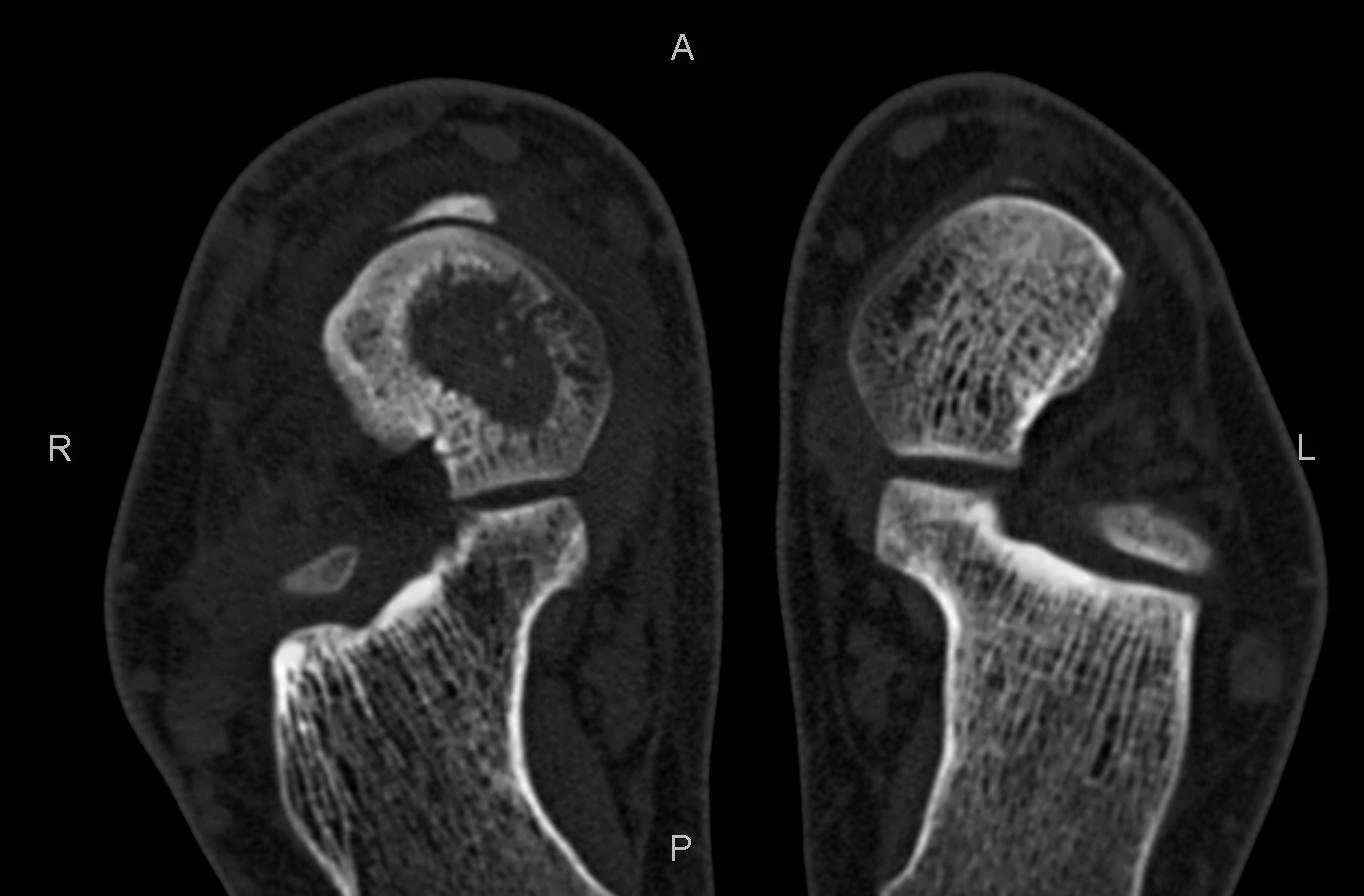

Уважаемые коллеги, обратился за помощью пациент, мужчина, 25 лет. С жалобами на болевой

синдром в области голеностопного сустава и среднем отделе стопы. Травму отрицает. Со слов,

болевой синдром в течении 1 года. Последние 1-1.5 мес периодически вынужден пользоваться

костылями. После ограничения нагрузки боли уменьшаются. Соматически здоров. До появления

болей активно занимался рукопашным боем.

На СКТ картина рассекающего остеохондрита блока

таранной кости, киста шейки таранной кости с признаками импрессии суставной поверхности. А

также - разрастания переднего края б\берцовой кости сопровождающиеся клиникой импиджмент

синдрома.